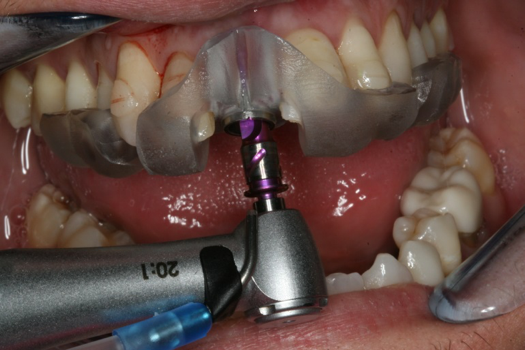

The next case follows the digital protocol for fully guided surgery and prosthetics. A CBCT radiograph, digital impression, and digital photography were the cornerstones to the success of this case. The 3D data set was electronically delivered to the dental laboratory. The data were merged and the process to develop the plan was initiated. The use of CBCT was essential in this case, particularly due to minimal space for placement of individual implants and single-unit crowns. The patient's chief concern was that she wanted to have single-unit crowns instead of fixed crown-and-bridge restorations because she was worried that she would someday find herself in an assisted-living facility; if that were to happen, she wondered, who would help floss under her bridge work? Her decision was to have single implants with individual crowns. CBCT technology is much more accurate in evaluating space maintenance and management.10 Periapicals in the past were rather close for calculating spacing; however, the CBCT identifies the buccal-lingual dimensions as well as the mesial-distal measurements. On review of the completed proposals for implant placement and provisionals, it was determined that there was sufficient spacing for implant placement to allow appropriate emergence profiles for the provisionals and then eventually the final single-unit cemented crowns. The proposal was accepted, and a 3D-printed surgical stent was fabricated, along with the PMMA provisionals (Figure 29 through Figure 35).

On the day of surgery, the plan was to extract teeth Nos. 21, 23, 24, 25, and 26, place 3.0 x 13-mm implants in the anterior region due to limited spacing, and place a 4.1 x 10-mm implant in the No. 21 extraction site. Before the extractions were performed, the No. 23 pontic was sectioned from the existing 2-unit cantilevered bridge utilizing ceramic and metal high speed rotary cutting burs ZR 6881 and H34L (Komet-USA), respectively. After removal of the pontic and extractions, the surgical guide was verified to be seating positively (Figure 36 through Figure 38). Surgical guide protocol was followed, and all implants were successfully placed and torqued to a value of greater than 35 Ncm (Figure 39 and Figure 40). All implants were placed without flapping, with the exception of No. 23. The flap was elevated to reposition lingual keratinized tissue facially for enhanced esthetic tissue profile. The implants were then prepared with a high-speed carbide bur (Komet-USA) with copious amounts of water (Figure 41 and Figure 42). The one-piece 3.0-mm diameter implant served the needs of the patient's spacing requirements. Inter-occlusal space requirements and path of draw were verified. The PMMA provisionals were air abraded and relined with crown-and-bridge material (Figure 43 through Figure 45).

Fig 36. Anterior central view.

Figure 36

Fig 39. Surgical guide in place.

Figure 39

Fig 40. 3 x 13-mm implants.

Figure 40

Fig 41. Abutment preparation.

Figure 41

Fig 42. Occlusal view of prepared implants.

Figure 42